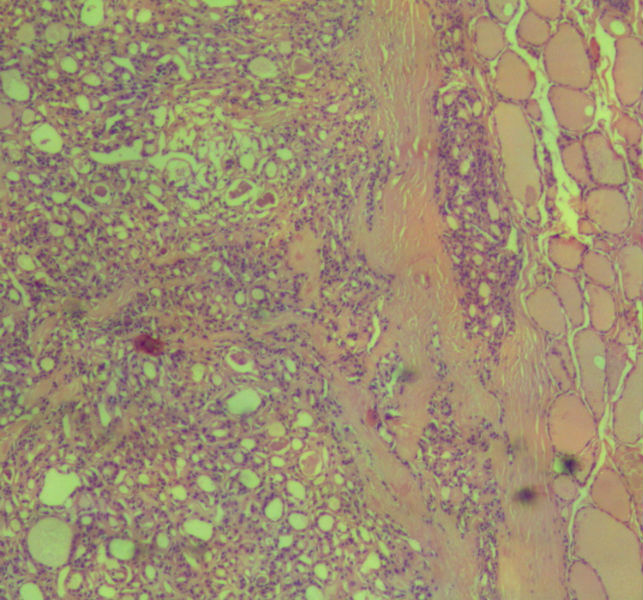

女,45岁,体检发现颈前区一结节,术中送检甲状腺左腺叶,发现一界清结小1*0.8cm,灰黄色。术中诊断滤泡性肿瘤伴包膜累及,局部疑包膜穿破,滤泡癌可能,待石蜡报告。石蜡连续切片形态见图,可见明显包膜穿破,诊断为滤泡性癌。患者借片到上级医院会诊,结果为:包膜内滤泡癌伴包膜累及。请问有包膜内滤泡癌的提法吗?这个病例怎么诊断啊?请各位老师多指导。

• 这个是滤泡性癌吗图3

图3

甲状腺滤泡癌确实分2型:浸润型包膜不完整,明显浸润周围甲状腺组织;包裹性血管浸润型有包膜,但有血管或包膜浸润。

本例包膜不完整,应该是滤泡癌。